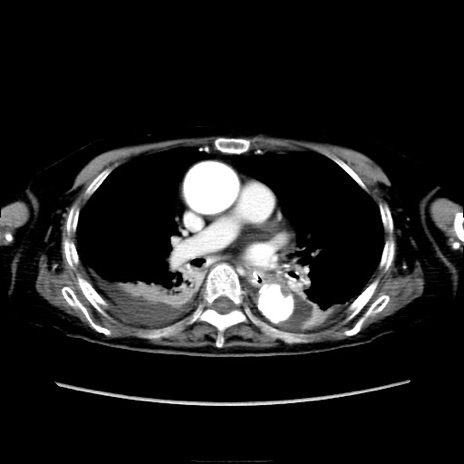

症例40(横断像)

横断像